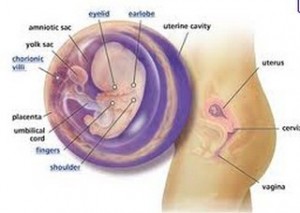

At 9 weeks pregnant your baby will be an inch long and weigh around one ounce or about the size of a large grape. But it won’t be long, the baby will grow real fast and he or she will get heavier as well. With an ultrasound device, you’ll also begin to hear the baby’s heartbeat. And the baby will begin to move, maybe spread its arms and legs or turn its head. But because the fetus is still too tiny you might not feel anything for the mean time.

During this period, you’ll find your baby in good form with arms and legs. Fingers and toes are likewise present. The baby’s nipples and the hair follicles will begin to form. The eye muscles and the upper lip will also be developed but the eyelids are still shut and would open until later in the baby’s development. The semicircular canals in the baby’s ear will begin to form as well. And as for the internal organs, the nerve connections in the retina and brain will be established. The intestines will move from the umbilical cord towards the inside of the baby’s abdomen. The urinary and the rectal passageway will completely be separated.